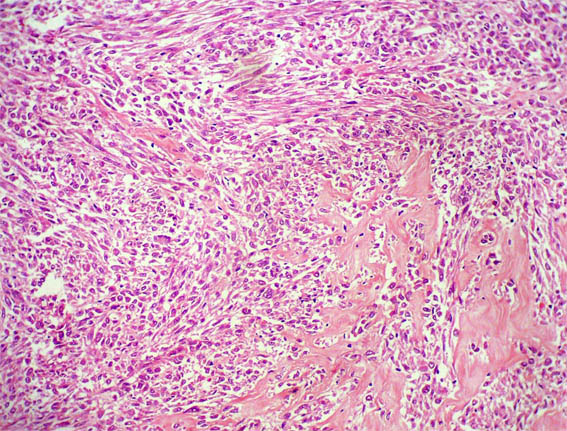

Figura 1.

H&E, X100.